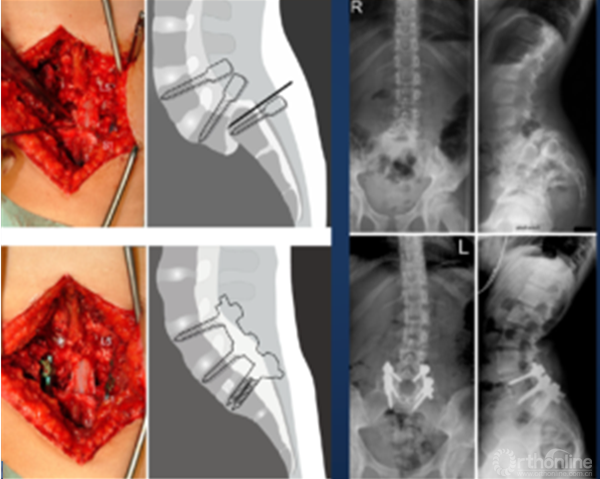

② 明显失平衡者,采取后路复位联合前路支撑重建术式。

① 采取前后联合,骶骨部分截骨、复位和椎间支撑重建手术[8]。

② 我们的病例